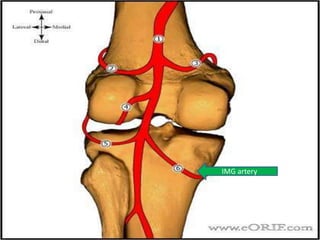

• Blood supply

– medial inferior genicular artery

– lateral inferior genicular artery

AnatomyPopliteal artery

Anatomy

ILG artery

IMG artery

Anatomy • Bloodsupply – medial inferior genicular artery – lateral inferior genicular artery

• #11 Blood supply 1-medial inferior genicular artery supplies peripheral 20-30% of medial meniscus 2-lateral inferior genicular artery supplies peripheral 10-25% of lateral meniscus central 75% receive nutrition through diffusion-This presents a problem when there is an injury to the meniscus, as the avascular areas tend not to heal without the essential nutrients supplied by blood vessels.